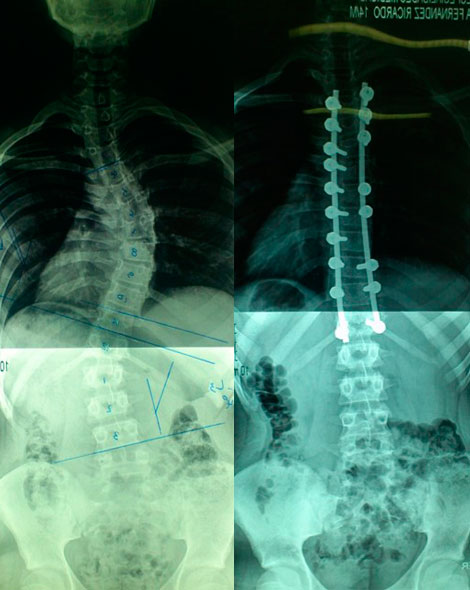

CIRUGIA:

¿Cuándo puede recomendarse la cirugía?

¿En que consiste la cirugía?